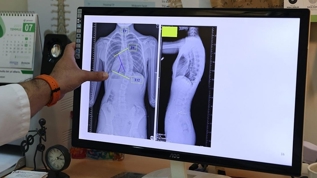

Ondokuz Mayıs Üniversitesi (OMÜ) Tıp Fakültesi Ortopedi ve Travmatoloji Anabilim Dalı Öğretim Üyesi Doç. Dr. Hüseyin Sina Coşkun, çocuklarda ergenlik öncesi skolyoz (omurga eğriliği) kontrolünün tedavi şansını artırdığını söyledi.

Ondokuz Mayıs Üniversitesi (OMÜ) Tıp Fakültesi Ortopedi ve Travmatoloji Anabilim Dalı Öğretim Üyesi Doç. Dr. Hüseyin Sina Coşkun, omurganın ön ve arka planında 10 dereceden fazla olan eğriliği skolyoz hastalığı olarak kabul ettiklerini belirtti.

Skolyozun özellikle kız çocuklarında daha sık görüldüğünün altını çizen Coşkun, ergenlik öncesi çekilecek bir omurga röntgeninin tedavide daha iyi yol alınmasını sağlayacağına işaret ederek, "Kız çocuklarında doğumsal kalça çıkığında olduğu gibi skolyoz yönünden tedbirli olmakta fayda var. Özellikle adet öncesi dönemde kızların en azından bir omurga röntgeninin çekilmesi, yine erkeklerde de ergenlik öncesi dönemde bir kez omurga röntgeninin çekilmesi olası bir skolyoz hastalığının tedavisine erken başlamak adına önemli. Çünkü tedaviye ne kadar erken başlarsak o kadar iyi sonuç alma ihtimalimiz yüksek." ifadelerini kullandı.